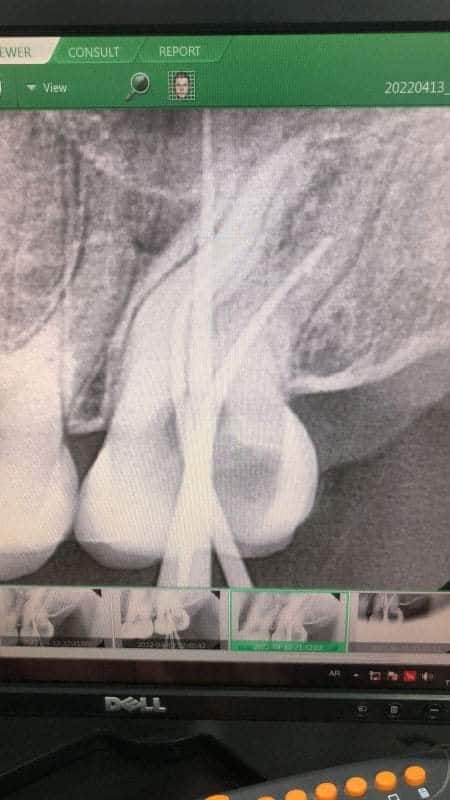

Radiographic picture send by my colleague

Showing inability of the Gp cones to reach apex in MB and DB canals because of ledges